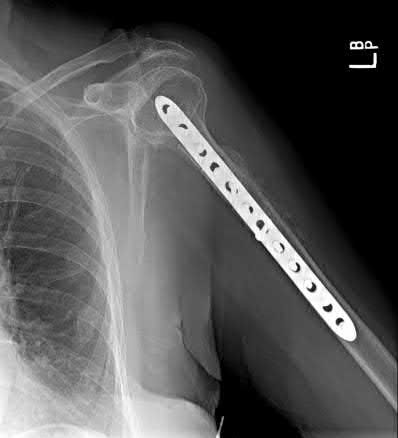

A 44-year-old male presents with the isolated injury seen in Figure A after a motor vehicle accident and underwent the operative treatment seen in Figure B within 8 hours from the time of incident. Which of the following complications is this patient at highest risk of developing?

This young male patient has sustained a displaced femoral neck fracture and underwent open reduction internal fixation with 3 cannulated screws. Based on the available options, the patient is most at risk of developing osteonecrosis of the femoral head.

Femoral neck fractures in young patients typically are the result of a high-energy trauma. Fracture displacement has been shown to disrupt vascular supply to the femoral head by interrupting retinacular vessels and ligament teres vascularization, as well as increasing intracapsular pressure, producing a tamponade effect. The incidence of osteonecrosis in patients younger than 60 years with displaced femoral neck fractures has been shown to be between 15-30%. Quality of reduction is one key factor that has been shown to influence outcomes postoperatively.

Loizou et al. prospectively studied 1,023 patients who sustained an intracapsular hip fracture that was treated with internal fixation using standard fixation modalities. They showed that osteonecrosis was less common for undisplaced (4.0%) than for displaced fractures (9.5%). The population at greatest risk were women younger than the age of 60 with displaced fractures.

Barnes et al. review subcapital hip fractures. They found that late segmental collapse was more common in displaced fractures in women younger than age 75 years than in those older than age 75 years treated with internal fixation.

Figure A shows a displaced, Garden 3/Pauwels III hip fracture. Figure B shows anatomical fixation with 3 cannulated screws.